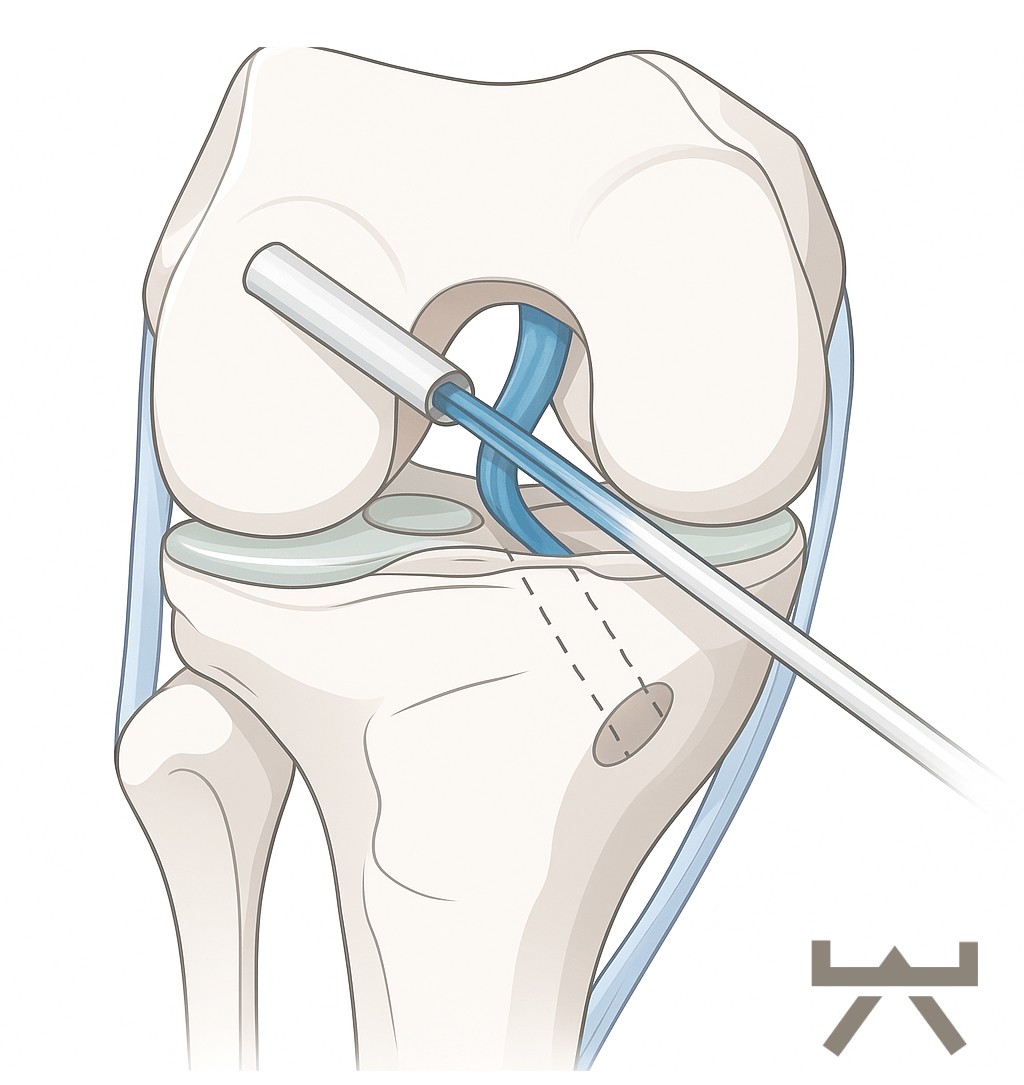

OPERATIONSARTEN

Während der Kreuzbandplastik wird das vorderste Kreuzband durch körpereigenes Sehnengewebe ersetzt. In den meisten Fällen findet die Operation arthroskopisch (mittels einer Gelenkspiegelung) statt. Als Transplantat für das Kreuzband werden vom Patienten entweder Teile der Beugesehnen (Semitendinosus-/Gracilis Sehne), oder das mittlere Drittel der Kniescheibensehne (Patellarsehne unterhalb der Kniescheibe oder Quadriceps Sehne oberhalb der Kniescheibe) entnommen. In seltenen Fällen ist ein Allograft (Spendersehne) oder ein Ersatz aus Synthetik Material notwendig. Es werden Bohrkanäle durch den Unterschenkel- und den Oberschenkelknochen vorgenommen, durch die das Transplantat dann durchgezogen und anschließend befestigt wird.

Es wurden viele Studien miteinander verglichen, um herauszufinden, welches Transplantat am besten für die Rekonstruktion geeignet ist. Hierbei konnten für alle oben genannten Transplantate vergleichbare Ergebnisse in sowohl klinischer als auch funktioneller Hinsicht, gefunden werden. Im Allgemeinen sind die in Frage kommenden Sehnen alle sehr wichtig für die Stabilität des Knies und können somit durch die Entnahme auch Beschwerden entstehen. Einen durch Studien belegter Vorzug des Transplantats der Quadrizepssehne im Vergleich zur Hamstring Sehne ist, dass an der Entnahmestelle signifikant weniger Beschwerden und Schmerzen auftreten.43

Kniesehne Kreuzband-Plastiken führen zu Veränderungen der Muskeleigenschaften, die allesamt zu einer reduzierten Kniebeugerkraft und Propriozeption (unbewusste Wahrnemung der eigenen Bewegung, Stellung, Spannung, Haltung und der Lage im Raum) des Kniegelenkes beitragen können. 32,68 Dies ist ein signifikanter Risikofaktor für die Entstehung von Kniegelenksarthrose.

Bei Verwendung einer Patellarsehnen Plastik konnte eine erhöhte Rate von Arthrose in der Bildgebung bzw. ein stärkerer Knorpelverlust dokumentiert werden. 14,49 Zusätzlich ändert sich die Biomechanik 5,46,49 und das Risiko von Patella Frakturen bzw. Patellarsehnenrupturen und die Schmerzen beim Knien nehmen zu (bis zu 46% geben Kniebeschwerden an). 23,28 Des Weiteren wird häufig ein andauerndes Streckdefizit von >5° festgestellt.

Bohrkanäle

Transplantatdurchzug